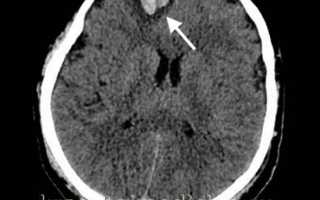

image

Аксиальная КТ головного мозга без контрастного усиления. Определяется контузионный очаг в правой лобной доле, представленный геморрагическим компонентом, зоной детрита и отека

Ушиб средней тяжести характеризуется наличием на томограммах очагов ушиба в виде зон пониженной плотности. При геморрагическом пропитывании очаг ушиба может иметь повышенную плотность. При тяжелом ушибе томография визуализирует очаги как повышенной, так и пониженной плотности. В первом случае речь идет о сгустках крови, во втором — об участках размозжения и отека. При крайне тяжелых поражениях зона деструкции церебральной ткани уходит вглубь к подкорковым структурам.